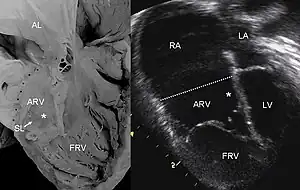

O Diagnóstico é feito pela ecocardiografia, onde demonstra conexão atrioventricular concordante, importante aumento do átrio direito, valva tricúspide displásica implantada caudalmente , com regurgitação sistólica massiva para a porção atrializada do ventrículo direito e para o átrio direito gigante. O ventrículo direito fica de tamanho reduzido, por diminuição de sua via de entrada atrializada. O tronco e os ramos da artéria pulmonar são confluentes, de calibre diminuído, com valva imóvel e fluxo retrógrado pelo canal arterial. O forame oval pequeno, com abaulamento fixo do septo interatrial da direita para a esquerda, com ausência de fluxo bifásico através do mesmo. Pode haver presença de pequeno derrame pericárdico.[3]